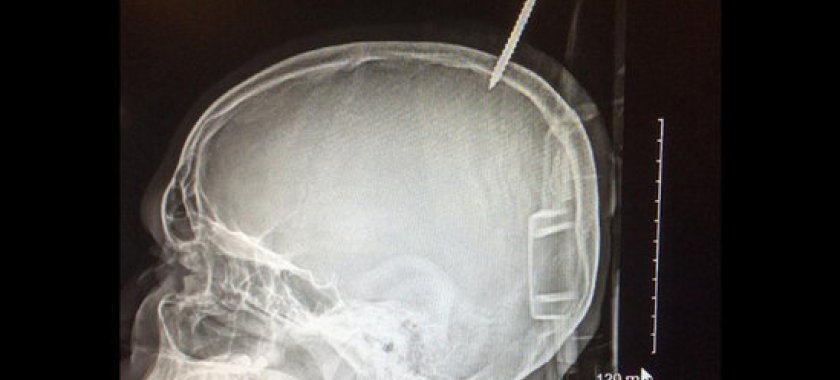

İcmal.Az yenicag.az-a istinadən xəbər verir ki, Darius Forman adlı yeniyetmə qardaşları ilə birgə ağacda taxta ev düzəltmək istəyiblər. Bu zaman o, ağacdan yıxılıb. Daha sonra isə onun başına iri taxta parçası düşüb. Taxtada olan şurup Dariusun kəllə sümüyündən girərək, beyninə ilişib. Xəstəxanaya çatdırılan uşaq təcili əməliyyat masasına uzadılıb. Lakin əməliyyatı həyata keçirtmək heç də asan olmayıb. Bunun üçün həkimlər öncə taxtanın bir hissəsini kəsib, daha sonra isə kəllə sümüyünü dələrək, şurupu çıxardıblar.

Deyilənə görə, şurup bir millimetr daha dərinə keçsəydi, oğlan qanaxmadan ölə bilərdi. Beləliklə, həkimlərin çoxsaylı səyləri nəticə verib və VII sinif şagirdinin həyatını xilas etmək mümkün olub.